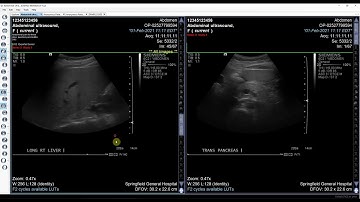

An introduction to OnePacs